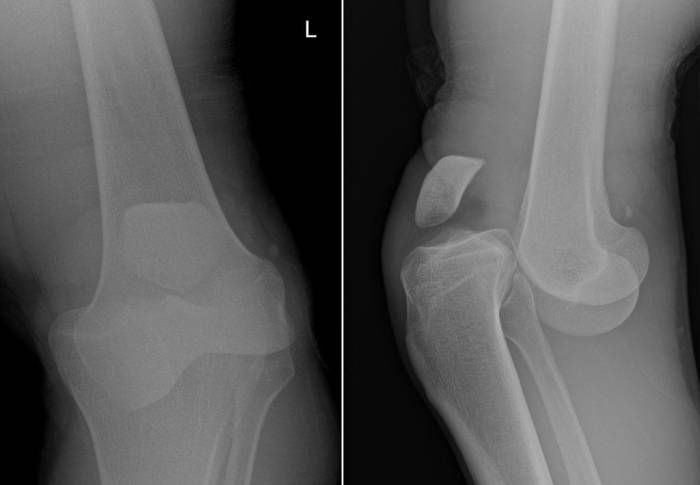

Диагностика вывиха колена и его типа включает следующие этапы:

1. Сбор анамнеза, визуальный осмотр и пальпация.

2. Рентгенография для определения характера смещения и исключения повреждений костей, а также для дифференциальной диагностики вывиха и повреждения мениска.

3. МРТ или компьютерная томография.

• Внешний осмотр. Выявление вывихов ББК не вызывает затруднений из-за заметного нарушения контуров сустава и отсутствия движений на фоне пружинящего сопротивления. Смещение надколенника также легко определяется визуально из-за деформации передней части колена.

• Рентгенография коленного сустава. Это основной инструментальный метод исследования. На рентгенограммах определяют тип (передний, задний, боковые) и степень (полный, неполный) вывиха ББК, а также выявляют сопутствующие переломы. При вывихах надколенника уточняют вариант смещения (вбок, с разворотом, с вклинением).

• Другие визуализационные методики. Эти методы являются вспомогательными и применяются для уточнения характера и тяжести повреждения мягких тканей, а также для выбора оптимальной тактики лечения. Для оценки состояния капсулы и связок могут назначаться МРТ и УЗИ коленного сустава.